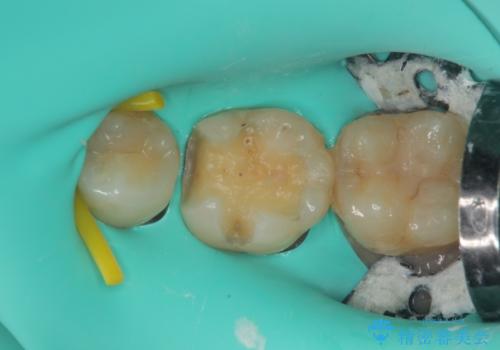

拡大鏡視野下で、メタルインレー、虫歯の除去を行い、セラミックインレーに適した形に整えました。

歯と歯茎の間に圧排糸と言われる糸を入れてシリコーン印象材にて精密な型どりをしました。